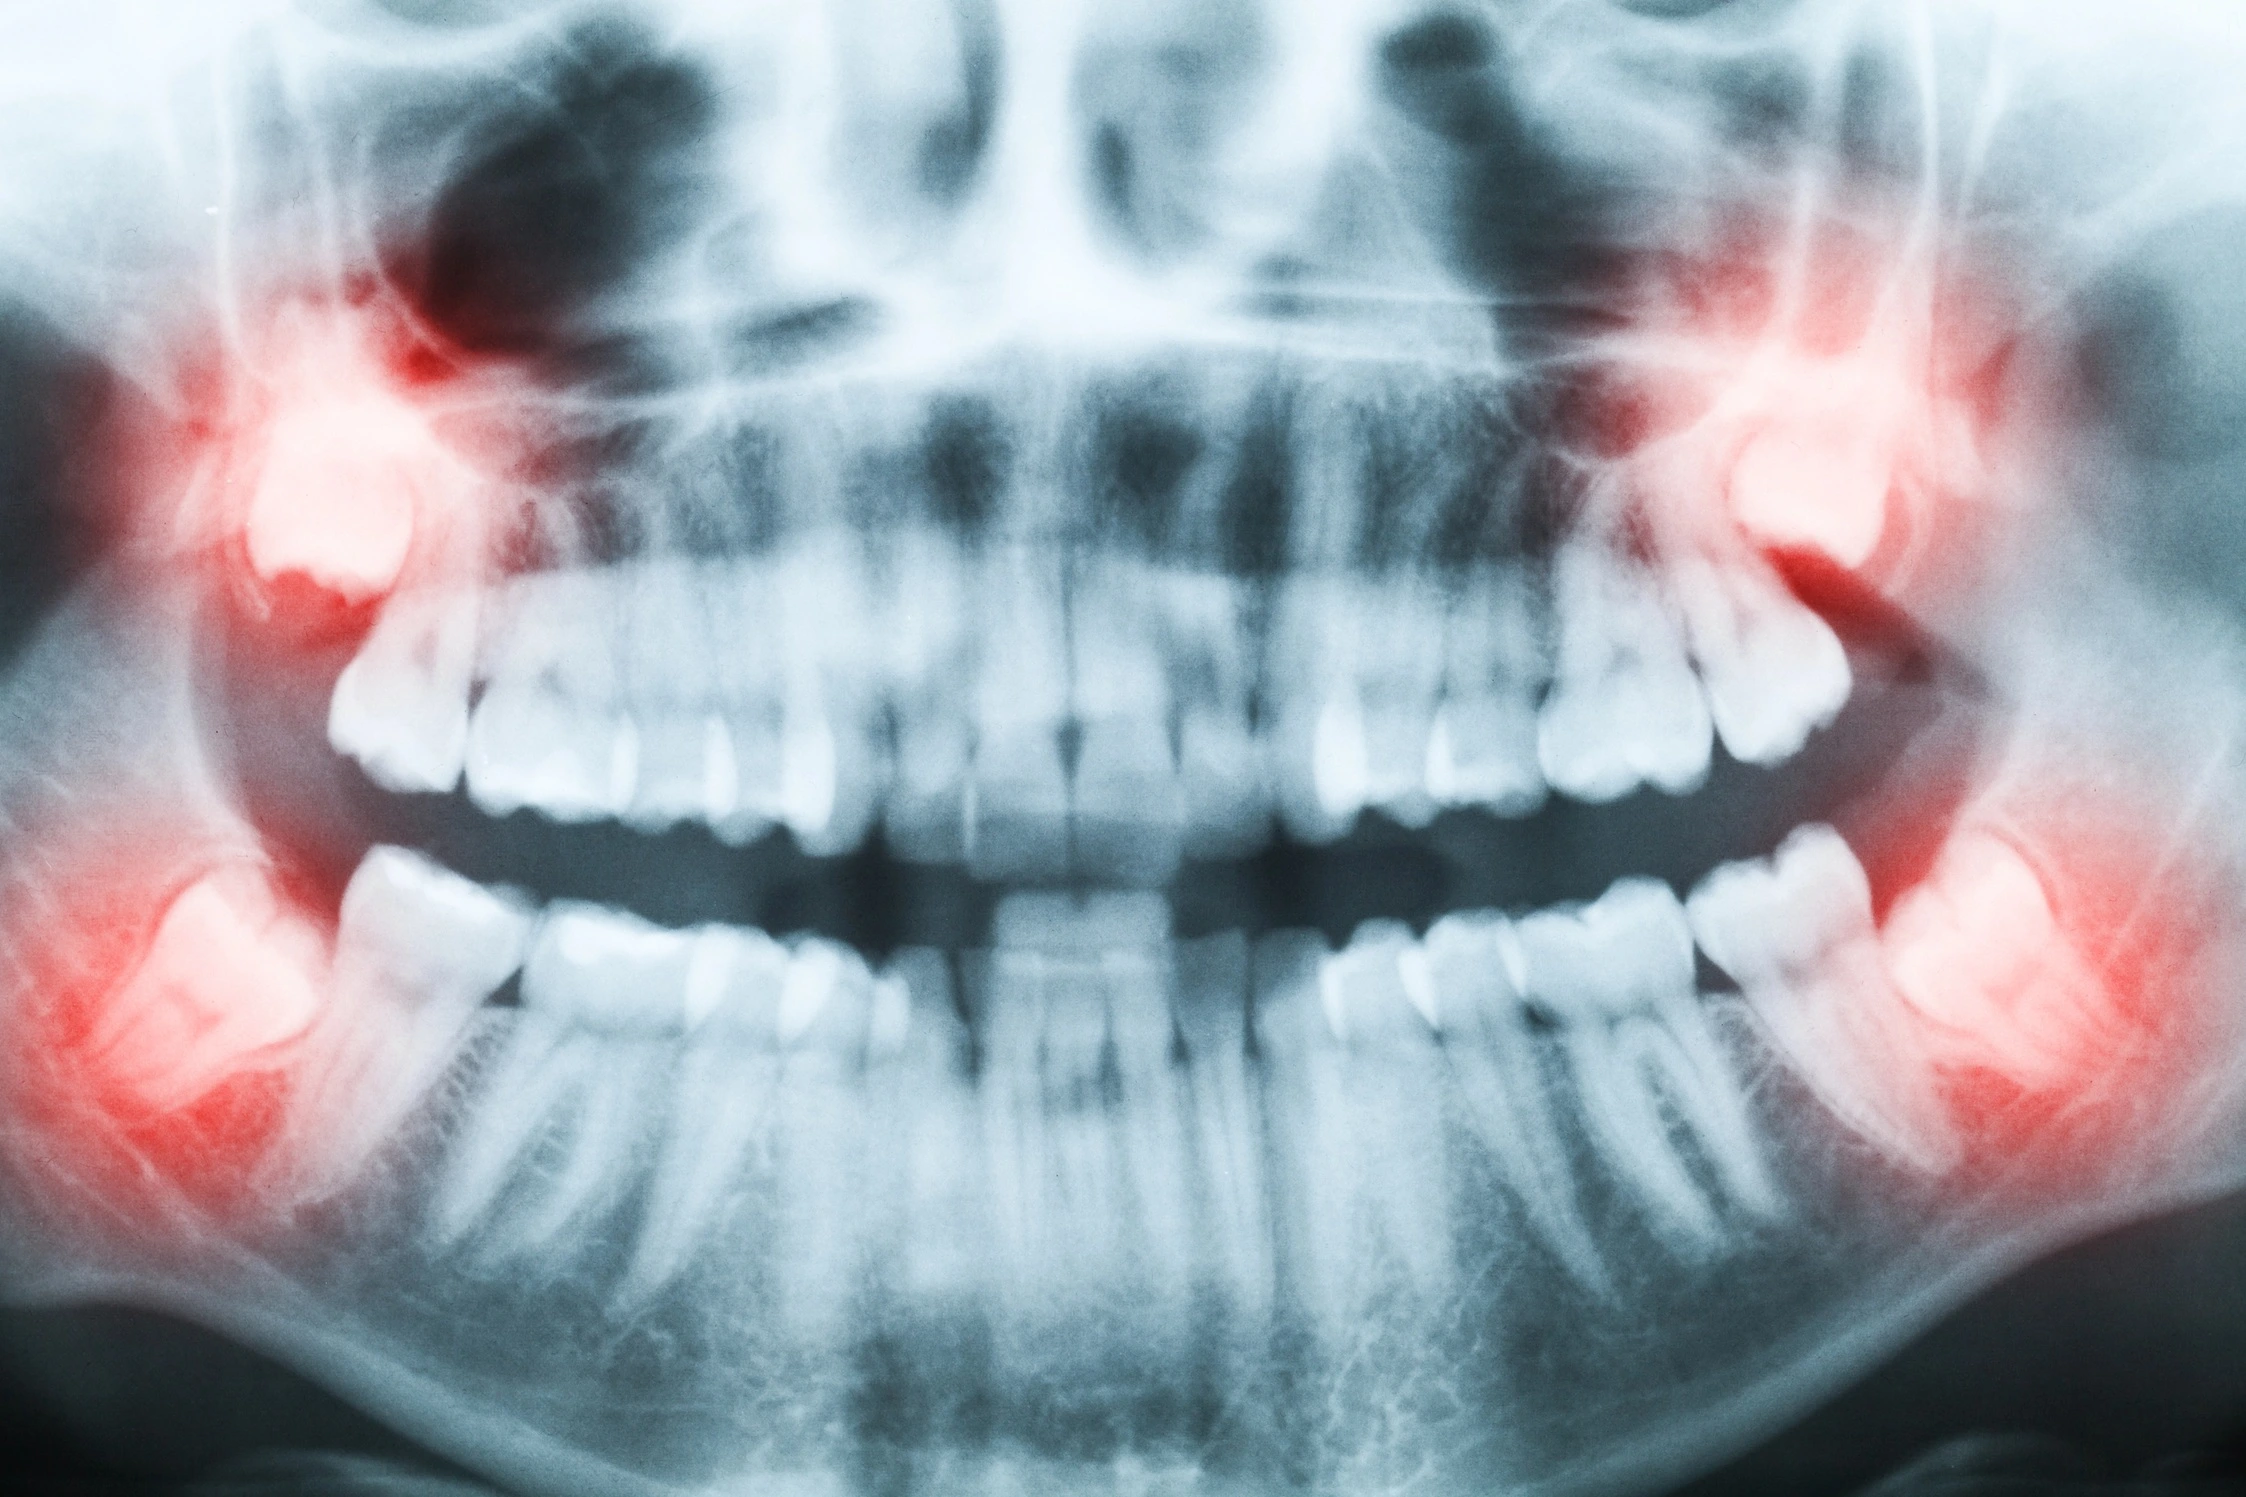

- Рентгенологическая диагностика — ключевой этап. Без снимка невозможно оценить истинное положение зуба мудрости. Делается прицельный снимок (ортопантомограмма, или ОПТГ) — панорамный снимок обеих челюстей. Он покажет:

- Направление роста зуба (ровное, горизонтальное, под наклоном).

- Состояние корней и их близость к нижнечелюстному каналу, где проходит нерв.

- Наличие кист или других патологических изменений вокруг зуба.